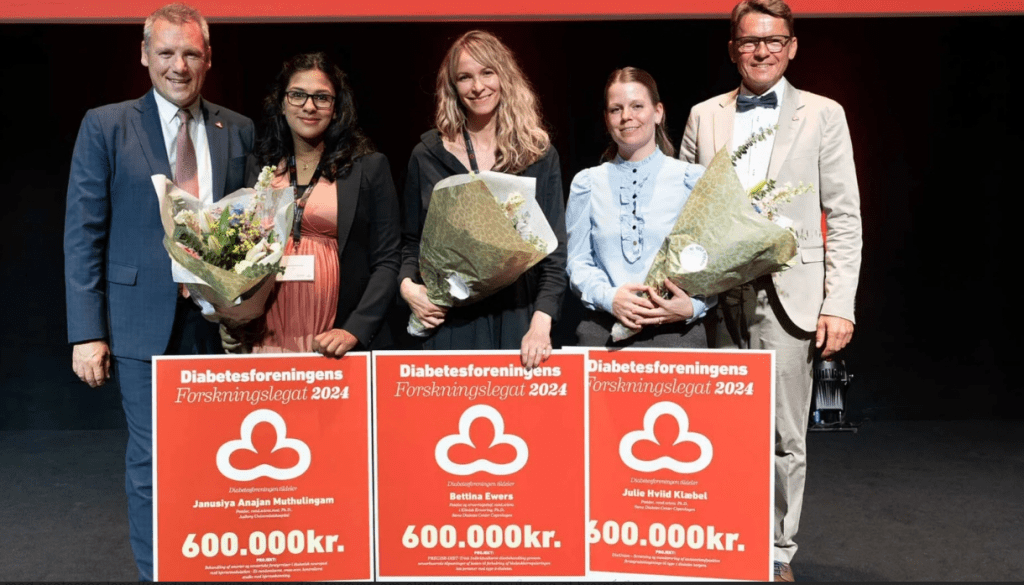

FORSKNINGSLEGAT FRA DIABETESFORENINGEN

Kan en hætte med elektroder forbedre livskvaliteten for mennesker med… Læs mere